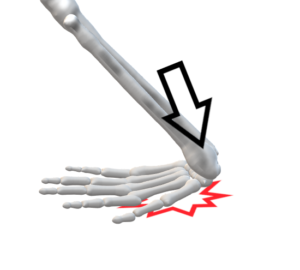

5.ショウファー骨折(橈骨茎状突起骨折)

(発生)

手関節に急激な撓屈強制

(整復)

月状骨関節面を支点とし手関節を尺屈し、橈側側副靭帯を緊張させ整復

(固定)

範囲:上腕から第1指を含めてギプス副子

肢位:肘90°、手関節尺屈